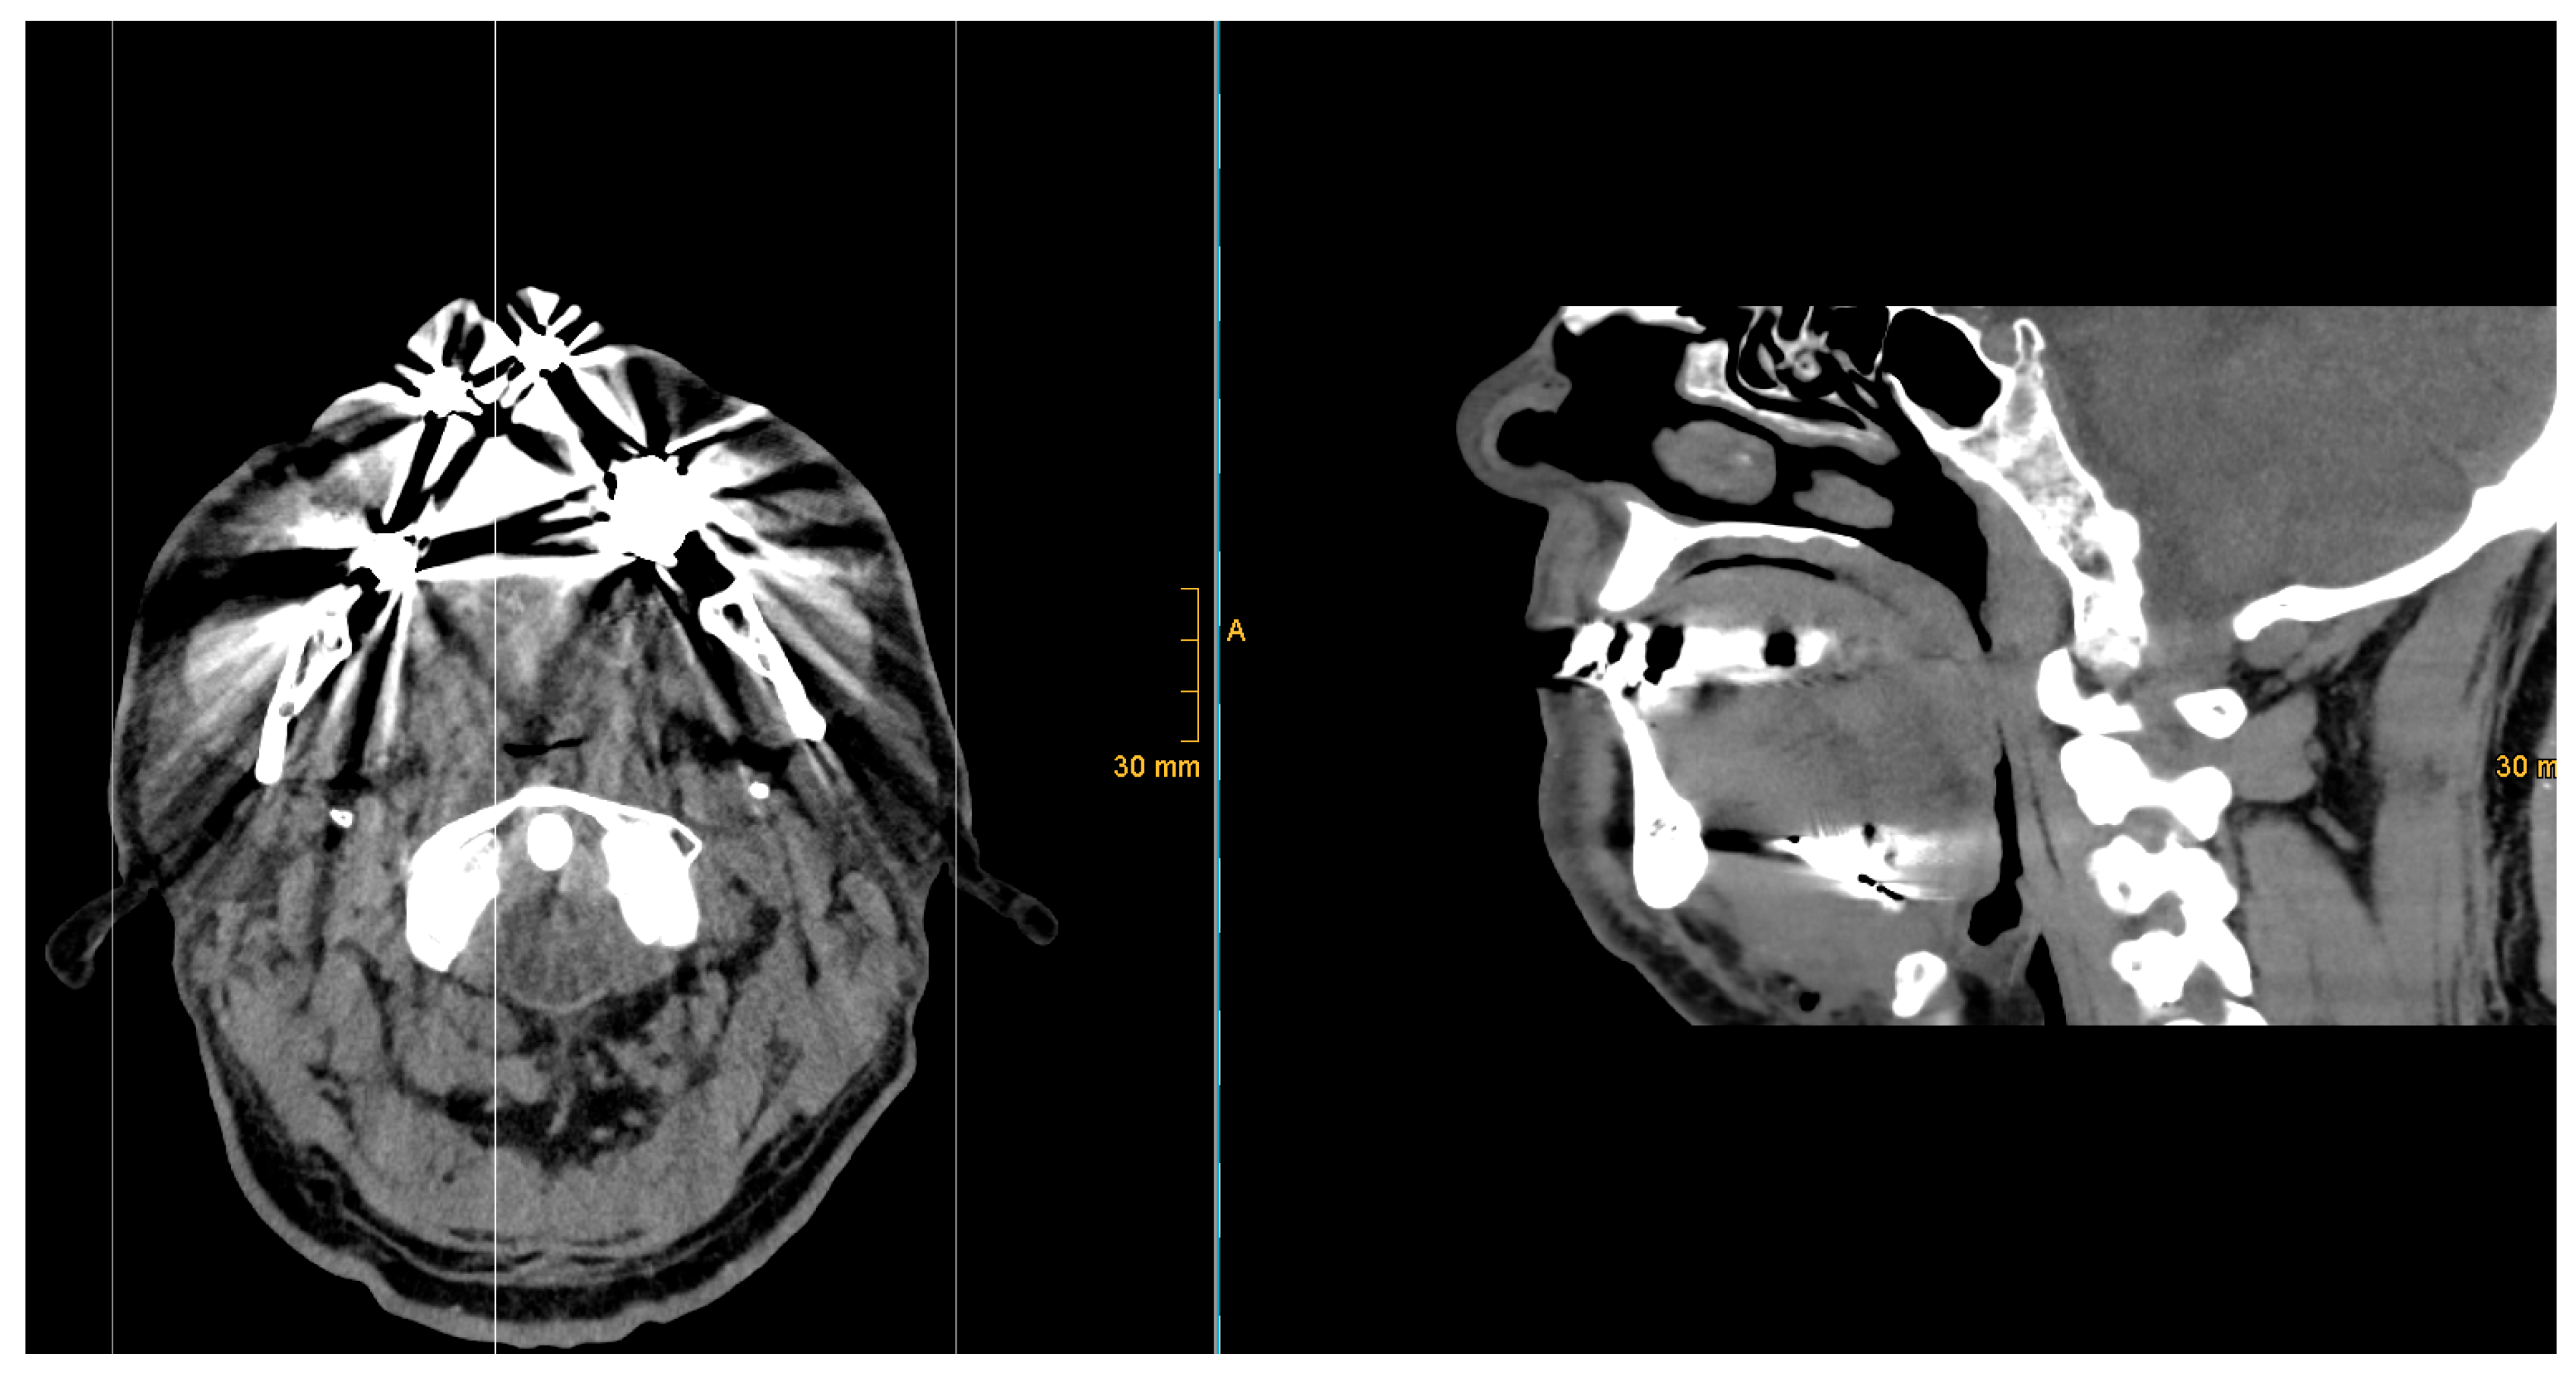

| 1 | 33 | 26 | yes | yes | yes | moderate | no | yes | 87,3 | 28,7 | 56,4 | 15,2 | 7,9 | 22,6 | -14,7 | asymmetry | 64,9 | proximal | proximal |

| 2 | 47 | 30 | yes | yes | yes | strong | no | yes | 94,1 | 45,7 | 57,0 | 19,0 | 18,7 | 19,3 | -0,6 | symmetry | 70,4 | proximal | proximal |

| 3 | 51 | 28 | yes | no | n/a | n/a | no | yes | 109,3 | 32,6 | 48,4 | 17,2 | 15,0 | 19,3 | -4,3 | asymmetry | 60,3 | proximal | proximal |

| 4 | 64 | 31 | yes | yes | yes | moderate | no | yes | 113,9 | 55,3 | 76,2 | 25,9 | 18,8 | 32,9 | -14,1 | asymmetry | 73,8 | proximal | proximal |

| 5 | 37 | 32 | yes | yes | yes | strong | no | yes | 93,2 | 23,9 | 54,5 | 15,4 | 13,9 | 16,9 | -3,0 | asymmetry | 35,3 | proximal | proximal |

| 6 | 52 | 25 | yes | yes | yes | moderate | no | yes | 86,0 | 20,3 | 47,1 | 15,8 | 15,6 | 16,0 | -0,4 | symmetry | 19,0 | proximal | distal |

| 7 | 28 | 28 | yes | yes | yes | moderate | no | yes | 102,0 | 36,7 | 64,3 | 16,4 | 14,4 | 18,3 | -3,8 | asymmetry | 40,7 | proximal | distal |

| 8 | 16,5 | 34 | yes | yes | yes | strong | no | yes | 122,3 | 32,1 | 77,9 | 12,5 | 18,4 | 6,6 | 11,8 | asymmetry | 39,9 | proximal | distal |

| 9 | 32 | 29 | yes | yes | yes | moderate | no | yes | 110,5 | 40,3 | 69,4 | 16,6 | 14,9 | 18,2 | -3,2 | asymmetry | 63,5 | proximal | proximal |